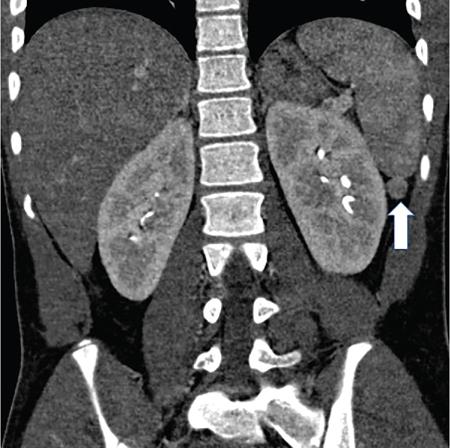

Kalpana Bansal, Poonam Narang The paediatric splenic abnormalities include both congenital and acquired pathological conditions. The congenital anomalies include variations in splenic number, location or fusion abnormalities and are more common than the acquired pathological conditions like splenomegaly, focal lesions, tumours and trauma. The splenic pathology can be evaluated with a wide variety of available imaging modalities including an ultrasound that is usually the first modality of choice in paediatric patients, computed tomography, magnetic resonance imaging and technetium-99m scintigraphy. The pattern-oriented approach to the radiological evaluation of splenic abnormalities may help to reach an accurate diagnosis and plan patient management. The congenital anomalies are common splenic abnormalities in paediatric patients. They usually result from absent or incomplete fusion of splenic lobules into one single organ before birth or abnormal location of the spleen. The congenital malformations include: The accessory spleen is commonly referred to as the splenunculus or supernumerary spleen. It results from the failure of the fusion of the primordial splenic buds in the dorsal mesogastrium during foetal life. The incidence is seen in 10%–30% of the population. The most common location of an accessory spleen is near the splenic hilum seen in about 75% of the cases and the pancreatic tail in 25% cases. It may be located anywhere along the course of the splenic vessels or in the abdomen and pelvis. The size of an accessory spleen ranges from few millimetres to centimetres and the number may vary from 1 to 6 (Fig. 9.21.1). The accessory spleens are usually asymptomatic and incidentally detected on imaging. But an accessory spleen present in an unexpected location can be misinterpreted as an abnormal soft tissue mass or lymph node. The characteristic imaging findings of the accessory spleen include similar imaging appearance to normal spleen on CT and MRI. The demonstration of feeding artery from the splenic artery can also be helpful in the differential diagnosis. Iron-containing MR contrast agents and Tc-99 sulphur colloid scintigraphy may be useful to confirm the diagnosis. The clinical significance of accessory spleen is seen in patients who had splenectomy for hypersplenism. In such patients, the accessory spleen may hypertrophy and result in recurrent disease; however, in patients of splenic trauma who had a splenectomy, it may help preserve the immune functions of the spleen. Splenopancreatic fusion is a rare anomaly that results due to abnormal fusion of splenic or pancreatic tissue as both organs arise from the dorsal mesogastrium close to each other. The ectopic splenic tissue may be located in the pancreatic tail (Fig. 9.21.2) and ectopic pancreas in the spleen or accessory spleen. It is also an incidental finding and asymptomatic. The clinical importance is to avoid complications during splenectomy or distal pancreatectomy. Splenogonadal fusion is an extremely rare anomaly that results due to the persistence of splenic tissue between the spleen and left testicle or epididymis. It may simulate masses and warrant unnecessary surgeries. The demonstration of splenic tissue connecting the spleen with the left gonad using any of the imaging modality helps in definitive diagnosis. Wandering or ectopic spleen is an extremely rare entity that results due to laxity or maldevelopment of the supporting splenic ligaments, and spleen can be found in any part of the abdomen. The incidence in several large studies of splenectomy is less than 0.5% and is mainly seen in children. The wandering spleen may be detected incidentally or present with different degrees of abdominal pain related to intermittent or acute torsion of the vascular pedicle. Ultrasound and CT remain the mainstay of diagnosis. Imaging findings include the absence of spleen in its normal position and a mass located anywhere in the abdomen or pelvis showing imaging and enhancement characteristics of normal splenic tissue. Besides, in the case of torsion, a typical ‘whirl’ pattern of the twisted pedicle and altered enhancement may also be demonstrated. Doppler shows absent flow within the spleen and low diastolic velocity with raised resistive index in the proximal splenic artery. The unenhanced CT shows hypoattenuation of the spleen, hyperdense intraluminal thrombus in the splenic artery and high density of the splenic capsule relative to parenchyma (‘rim’ sign). The contrast-enhanced CT shows absent or heterogeneous enhancement. The treatment modality of choice is splenopexy; however, splenectomy may be indicated in cases of infarction. Polysplenia and asplenia are typically seen in association with situs ambiguous or heterotaxia. Situs ambiguous with asplenia also known as Ivemark syndrome refers to right isomerism or bilateral right-sidedness and is characterized by an ambiguous location of abdominal organs with congenital absence of the spleen. It is more prevalent in males and associated with congenital heart disease in almost all cases (Fig. 9.21.3). Most patients die within the first year of life due to associated severe congenital heart disease and immunodeficiency due to absent spleen. Situs ambiguous with polysplenia is referred to as left isomerism or bilateral left sidedness. It is more common in females. The spleen may be located on the left or right side of the upper abdomen, the number may vary from 2 to 6 and diameter ranges from 1 to 6 cm (Fig. 9.21.4). The coexisting anomalies include a right-sided stomach, a midline or left-sided liver, bowel malrotation, short pancreas, absent gallbladder and associated inferior vena cava anomalies. Splenosis is an acquired anomaly that occurs following splenic trauma or splenectomy. It results due to auto-transplantation of splenic tissue usually in the peritoneal cavity but also may occur in extraperitoneal locations like the thoracic cavity. Splenosis is usually asymptomatic and incidentally detected on imaging. Splenosis is an acquired condition so it has distorted architecture and is supplied by surrounding vessels so, it can be mistaken for neoplastic lesions and lead to unnecessary surgery. A patient who had splenectomy for hypersplenism, splenosis may result in recurrent disease. However, a functioning splenic tissue may be required to preserve normal immunological function and remove old blood cells. Splenomegaly is a nonspecific finding seen as a manifestation of various disease processes listed in Box 9.21.1. CAUSES OF SPLENOMEGALY Ultrasound is usually the first and useful modality to evaluate enlarged spleen. It accurately measures the splenic span and also assesses the splenic echotexture, homogeneous or heterogeneous. Doppler USG is very good for the assessment of portal hypertension as a cause of splenomegaly by demonstrating flow in the splenoportal axis and collaterals. Both USG and CT also assesses the ancillary findings like lymphadenopathy in case of lymphoma or tuberculosis. Portal hypertension is one of the most common noninfectious causes of splenomegaly in children. Patients usually present with significant gastrointestinal bleed or massive splenomegaly. The causes of portal hypertension may be prehepatic, intrahepatic or posthepatic. The portal vein thrombosis is mostly idiopathic in children and results in collateral vessel development at porta known as cavernous transformation of the portal vein or portal cavernoma and portosystemic collaterals with massive splenomegaly (Fig. 9.21.5).